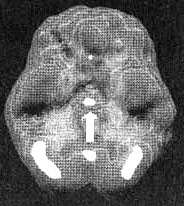

Мозг Брайана

Трехмерное изображение — активный мозг, вид сбоку. Обратите внимание на выраженное повышение активности поясной системы.

В семейном анамнезе у Брайана были случаи алкоголизма, депрессии и обсессивно-компульсивного расстройства. Никакими замечаниями не удавалось заставить его не держать руки во рту. Кроме того, Брайан был упрям, из-за чего у него были проблемы в школе. По словам учительницы, он «постоянно зацикливался на каких-то мыслях» и невнимательно работал в классе. Несколько месяцев индивидуальной терапии успеха не принесли. Я назначил SPECT, чтобы оценить функциональное состояние его мозга. Исследование выявило выраженное усиление активности в верхней средней части фронтальных долей (поясная система, с которой вы познакомитесь очень близко). Эта часть мозга позволяет нам переключать внимание с одного объекта на другой. Когда активность в этой зоне сильно повышена, люди начинают фиксироваться на идеях или типах поведения. Поскольку у Брайана в этой зоне отмечалась выраженная гиперактивность, я назначил ему малые дозы препарата Zoloft. Другое название этого препарата сертралин. Это антидепрессант, помогающий и при навязчивых состояниях. Замечено, что сертралин оказывает «охлаждающее» действие на поясной отдел головного мозга. Через несколько недель навязчивое вырывание зубов сошло на нет, а сам Брайан стал внимательнее на уроках в классе.